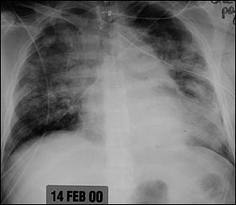

| Acute Respiratory Distress Syndrome |